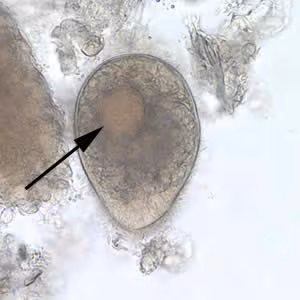

A group of refugees from Southeast Asia were being screened for parasites as part of a medical evaluation. Stool specimens were collected and processed. Examination of a wet mount from a formalin-ethyl acetate (FEA) concentration of one individual’s specimen revealed the object seen in Figure A. The objects were seen in low numbers and measured approximately 75 µm in length. What is your diagnosis? Based on what criteria?

Figure A